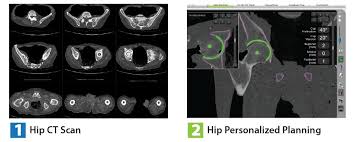

CT SCAN Each patient requires a pre-operative CT scan for the Mako TKA procedure. The Mako is a robotic arm-assisted surgery system transforming the way joint replacement surgery is performed.

Rdr2 thoroughbred black chestnut. Scan Location and Characteristics PositionLandmark Supine Feet First Topogram Scout Direction Cranio-Caudal. Cranio-maxillofacial CT Scanning Protocol Please keep in mind the following key points Please use a 3D scanning routine that provides high resolution images as would be suitable for image guided surgery stereotactic planning or other 3D applications. PDF 200004 CT Scanning Protocol Knee Arthoplasty GOMILCI 11A 2253 DESTRNIK ID za DDV. Rdr2 thoroughbred black chestnut. The initial step was determining the accuracy of the segmentation procedure. Final bone preparation trialing and implantation steps are executed with Triathlon Instruments as indicated in this technique. Knee 20 - 50mm interval spacing throughout the scan Axial slices 11 pitch using helical spiral scanning FOV. This scan must follow the protocol in the Mako Knee CT Scanning Protocol PN 200004.

This article aims to. This scan must follow the protocol in the Mako Knee CT Scanning Protocol PN 200004 INSTRUMENTATION The Mako TKA Instrumentation and Disposables. Introduction This surgical protocol describes the technique and instruments utilized to implant the Triathlon Knee during a Mako Total Knee procedure. MAKO TKA IMPLEMENTATION A. Mako Knee Instrumentation Mako Knee ArrayBalancing Kit. Cranio-maxillofacial CT Scanning Protocol Please keep in mind the following key points Please use a 3D scanning routine that provides high resolution images as would be suitable for image guided surgery stereotactic planning or other 3D applications. In the operating room your surgeon guides Makos robotic arm to remove the arthritic bone and cartilage from the knee.